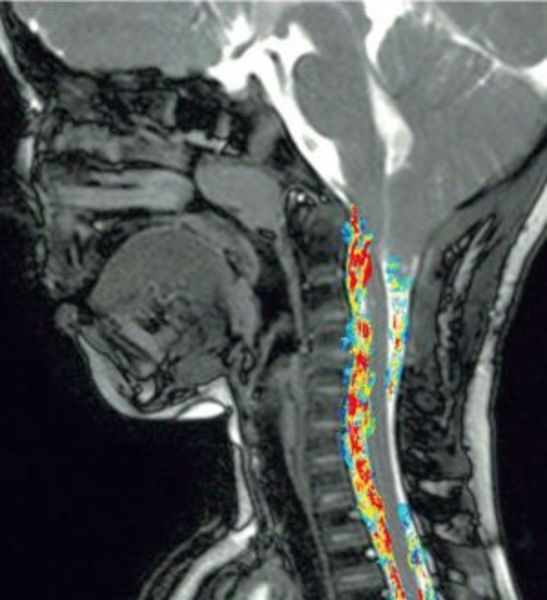

Zu den Weiterentwicklungen der letzten Jahre zählen unter anderem innovative Verfahren zur nicht-invasiven, farbkodierten Bildgebung und quantitativen Analyse der Flusseigenschaften des zerebro-spinalen Liquors Auch bei der Diagnostik und Verlaufskontrolle entzündlicher und tumoröser Erkrankungen des zentralen Nervensystems haben sich die Möglichkeiten der MR erweitert. Beides kommt zur Sprache bei dem Fachtreffen, das das Institut für Klinische Radiologie (IKR) des Universitätsklinikums Münster in Zusammenarbeit mit der Akademie für Fort- und Weiterbildung in der Radiologie ausrichtet. Neben institutseigenen Referenten konnten die Organisatoren mehrere international bekannte Experten für das Symposium gewinnen, das auf interaktive Wissensvermittlung setzt.